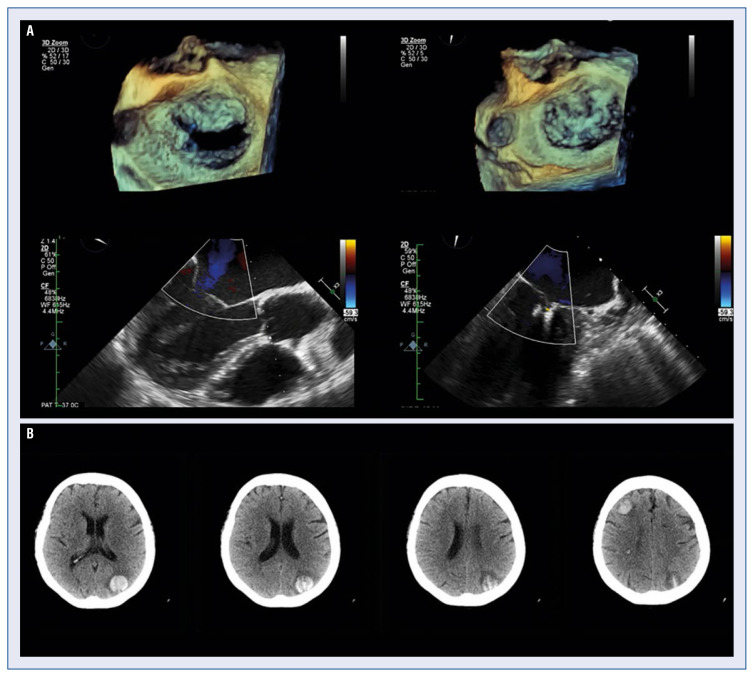

二尖瓣功能障碍影响着约2%的人口,其发病率仍在增加,是仅次于主动脉瓣狭窄的第二常见瓣膜性心脏病。根据疾病的病因,可分为原发性或继发性二尖瓣反流。治疗的第一道防线是最佳的药物治疗。如果无效,可以考虑二尖瓣介入治疗。对于不符合手术治疗条件的患者,可以考虑使用MitraClip进行经导管边缘到边缘修复。已经进行了超过100000次MitraClip手术,这使其成为治疗严重二尖瓣反流的最成熟的经导管技术。本综述的目的是根据目前可用的证据和临床经验,讨论MitraClip手术的技术细节、关于MitraClib疗效的临床证据、与夹子植入相关的并发症以及急性并发症。

Mitral valve dysfunction affects around 2% of the population and its incidence is still increasing, making it the second most common valvular heart disease, after aortic stenosis. Depending on the etiology of the disease, it can be classified into primary or secondary mitral regurgitation. The first line of treatment is optimal medical therapy. If ineffective, mitral valve intervention can be considered. For patients disqualified from surgical treatment, transcatheter edge-to-edge repair with the use of MitraClip may be considered. Over 100,000 MitraClip procedures have been performed which makes this the most established transcatheter technique for the treatment of severe mitral regurgitation. The aim of this review is to discuss the technical details of the MitraClip procedure, clinical evidence regarding the efficacy of MitraClip, complications related to the clip implantation alongside with acute complications based on the currently available evidence and clinical experience.